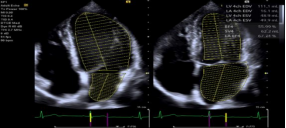

eSie Left Heart 自动左心分析

‒ 提高工作效率和检查流程

‒ 自动识别并描记经胸检查的左心室和左心房,并给出测量结果

‒ 基于经胸两腔心和四腔心图像,可进行在机或脱机分析